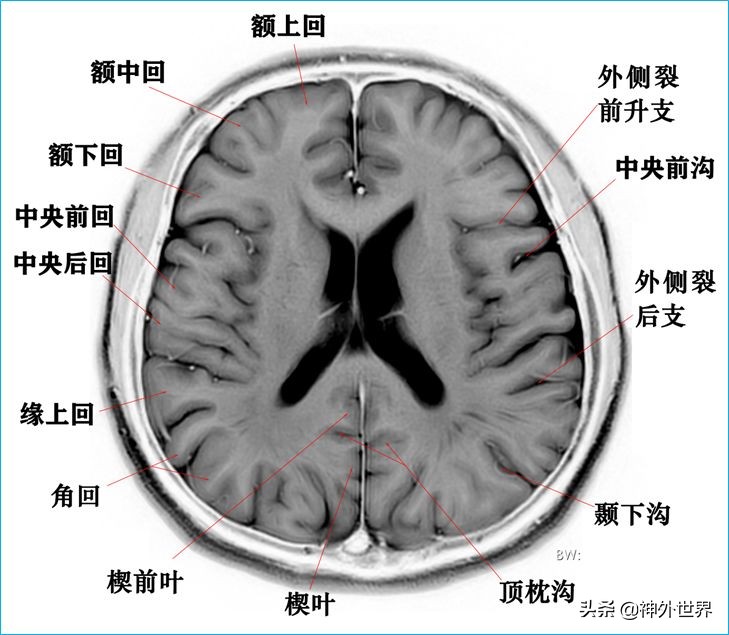

1、水平位连续切片

以下图片均来自我院3.0T核磁共振的T2WI反相图。标注均为我自己完成,水平有限,难免有误,还望各位老师多多指正。谢谢。